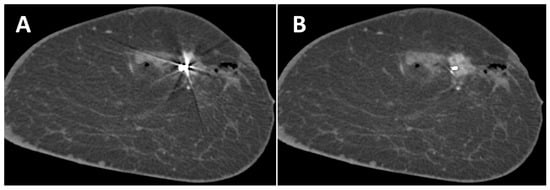

3.2. Effect of MAR on Artifacts